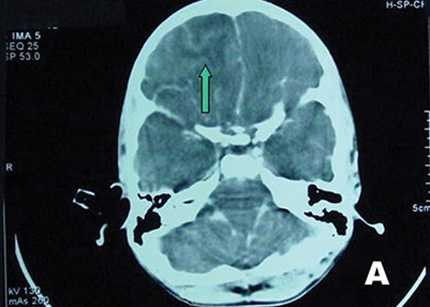

Tại BV Bệnh Nhiệt đới, BN sốt 39 độ C, lơ mơ, cổ cứng, thở nhanh 30 lần/phút. Kết quả xét nghiệm soi dịch não tủy không thấy có vi trùng lao hay vi nấm gây viêm màng não nhưng lại có sự hiện diện của một loại amip.

Sau đó, bệnh nhân vẫn sốt cao, 40 - 41 độ C, suy hô hấp, xuất huyết tiêu hóa và rơi vào tình trạng hôn mê sâu. Đến 23g ngày 31/7, BN nhiều lần bị ngưng tim đột ngột, tử vong.

Sau khi anh T. tử vong, BV Bệnh Nhiệt đới tiếp tục làm nhiều xét nghiệm và kết quả xét nghiệm sinh học phân tử PCR cho thấy anh tử vong do “amip ăn não người” tấn công.